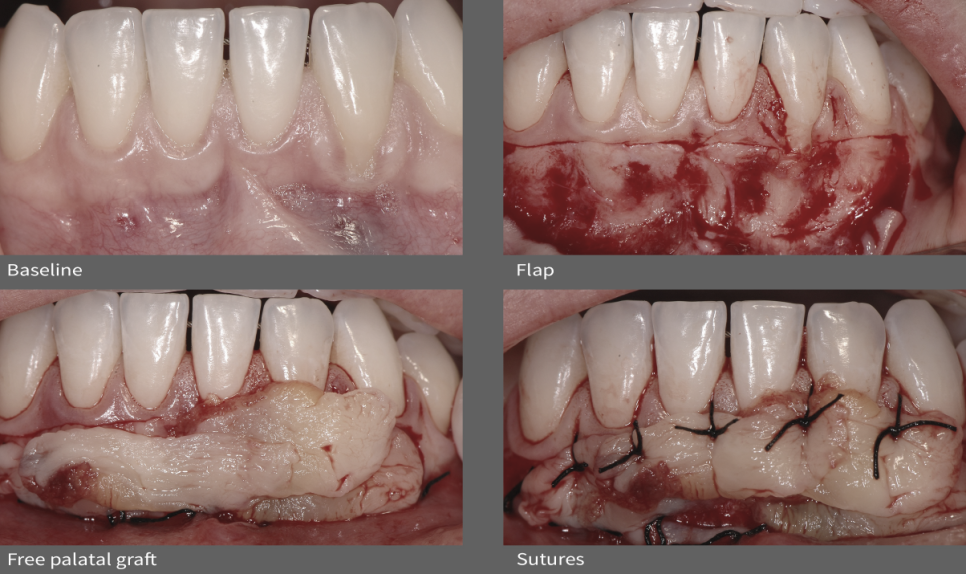

논문 속에 소개된 임상케이스

전문가 구강위생 관리 후 1주일 잇몸 퇴축 모습

이식 부위를 절개 및 플랩 생성

입천장에서 떼어낸 치은 조직을 위치시키고 봉합

수술 후 6개월 / 1년 / 2년 / 3년 후 모습